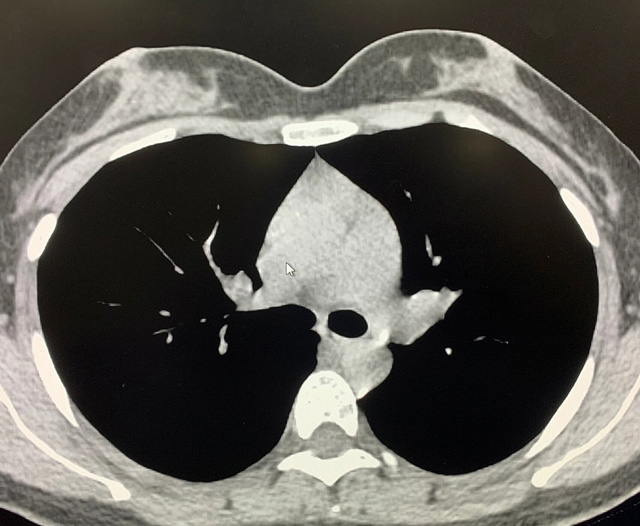

能谱纯化技术CT低剂量胸部扫描

能谱纯化技术的核心是通过物理滤过(如锡滤片)或软件算法,选择性滤除低能X射线光子,保留高能光子。在胸部低剂量CT扫描中显著提升了图像质量与辐射剂量的平衡。

2.明显提高图像质量,高能光子穿透力强,光子通量更均匀,图像噪声(标准差)可降低20%-40%。

优势辐射剂量显著降低相较于常规CT,辐射剂量减少约70%-90%,尤其适合需多次随访的高危人群(如肺癌筛查),降低辐射相关癌症风险早期肺癌筛查效果明确可清晰检测毫米级肺结节,显著提高早期肺癌检出率,降低死亡率。检查快捷且普及性高单次扫描仅需数秒,无需对比剂,设备广泛配置于基层医院,便于大规模筛查。长期成本效益显著虽单次费用与常规CT相近,但早期干预可大幅降低晚期治疗费用及社会医疗负担。技术优化提升图像质量迭代重建算法(如ASIR、MBIR)在降低剂量同时减少噪声,平衡影像质量与安全性。

1.图像噪声增加低剂量可能影响微小病变(如磨玻璃结节或支气管内病灶)的清晰度,肥胖患者图像质量下降更明显。